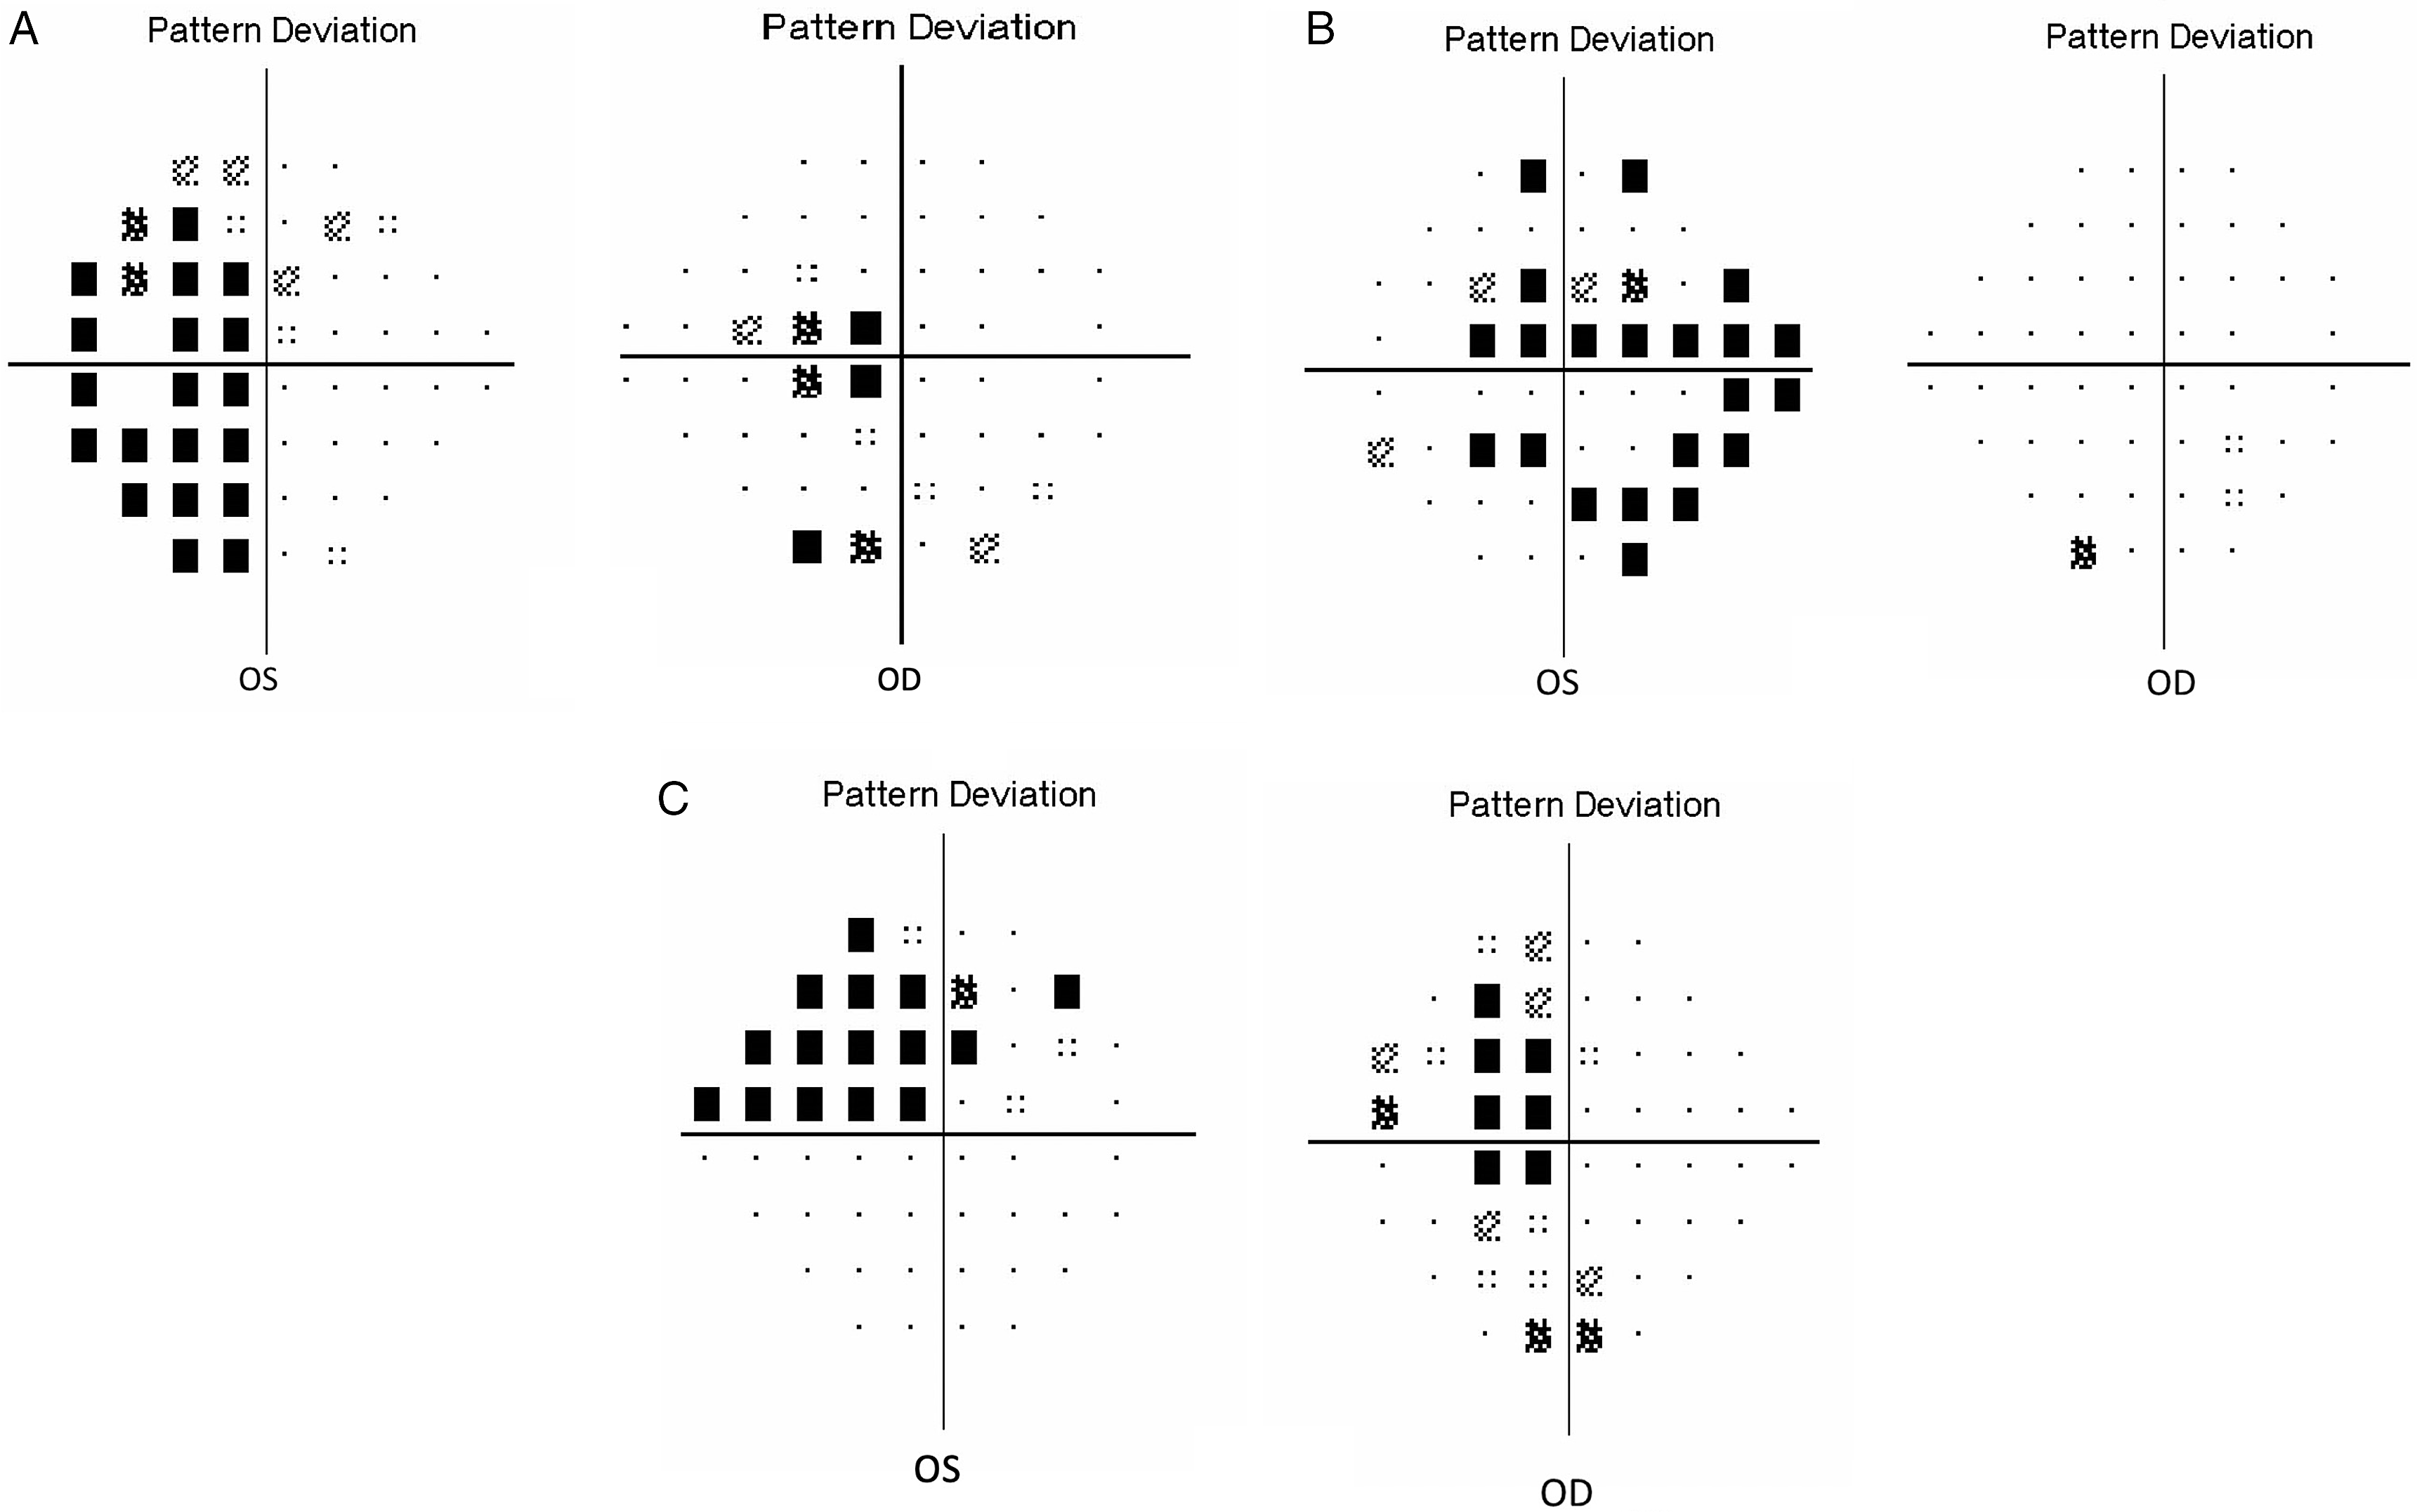

96.5% (28/29) of patients remained stable from the visual perspective during follow-up visits. Figure 1 details HVFs for patients 8, 13, and 24. Figure 2 includes details on T2-weighted MRI images for these patients. Two among the five patients with optic tract compression showed matching homonymous visual field defects (cases 9 and 24). Case 24 presented with significant compression on optic tract and optic chiasm by dolichoectatic basilar artery and showed progression of homonymous quadrantanopia to incongruous homonymous hemianopia. All other patients have remained stable without worsening of vision or visual fields.

Figure 1: 24–2 SITA Humphrey visual fields. (A) Patient # 24. Incongruous left homonymous hemianopia. Neurovascular compression: Right optic tract and dolichoectatic basilar artery. (B) Patient # 13. Left biarcuate defect. Neurovascular compression: Left pre-chiasmatic optic nerve and left ACA. (C) Patient #8. Incongruous left homonymous quadrantanopia. Neurovascular compression: Right optic tract and right ACA.